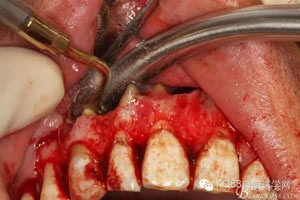

圖3.局部麻醉下,行唇側(cè)21垂直切口+齦溝內(nèi)水平切口

圖4.翻瓣、去除覆蓋在囊腫表面骨質(zhì),暴露出囊壁。